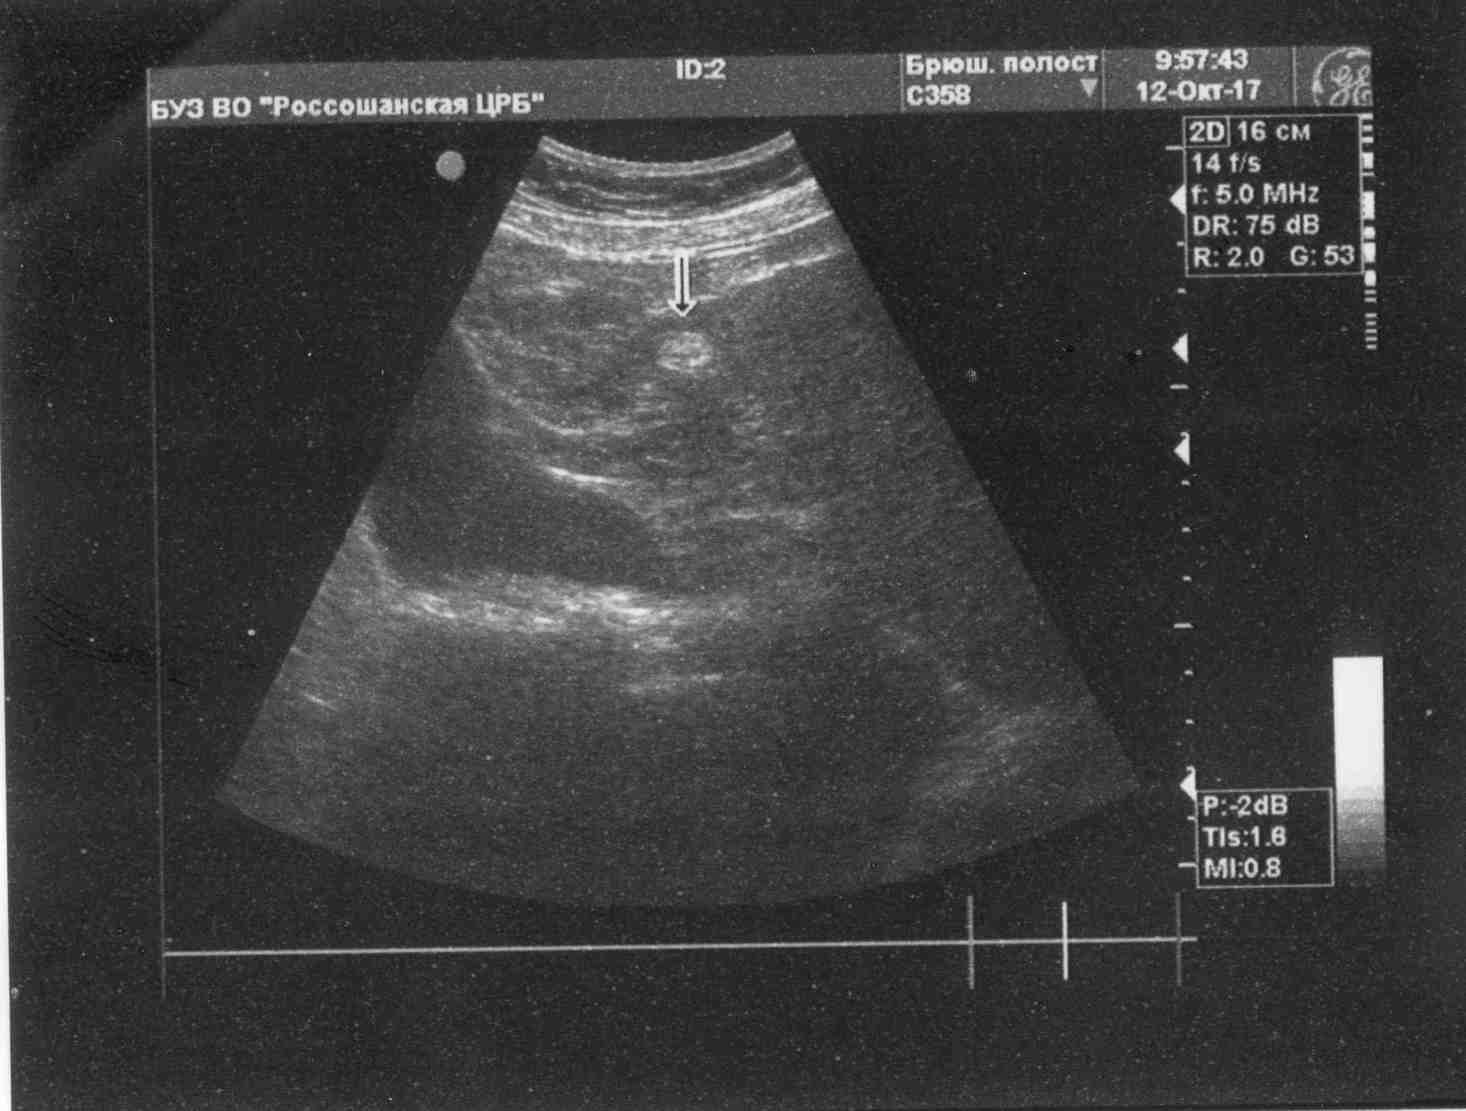

Вот только получилось взять УЗИ у отца.

Посмотрите, пожалуйста.

Есть плюсы и минусы по УЗИ (в сравнении со старым).

Печень стала больше, портальная вена - тоже. Селезенка увеличена, что часто бывает при высоком фиброзе.

Описание УЗИ желает быть лучшим... Очень неполное.

В желчном включения стали меньше по размерам - это хорошо!

В левой доле печени округлое эхо-включение (гемангиома, вроде), что раньше не было.

Нужна консультация гастроэнтеролога.

Раз в полгода нужно повторять УЗИ - отслеживать эти включения (и в желчном, и в печени).